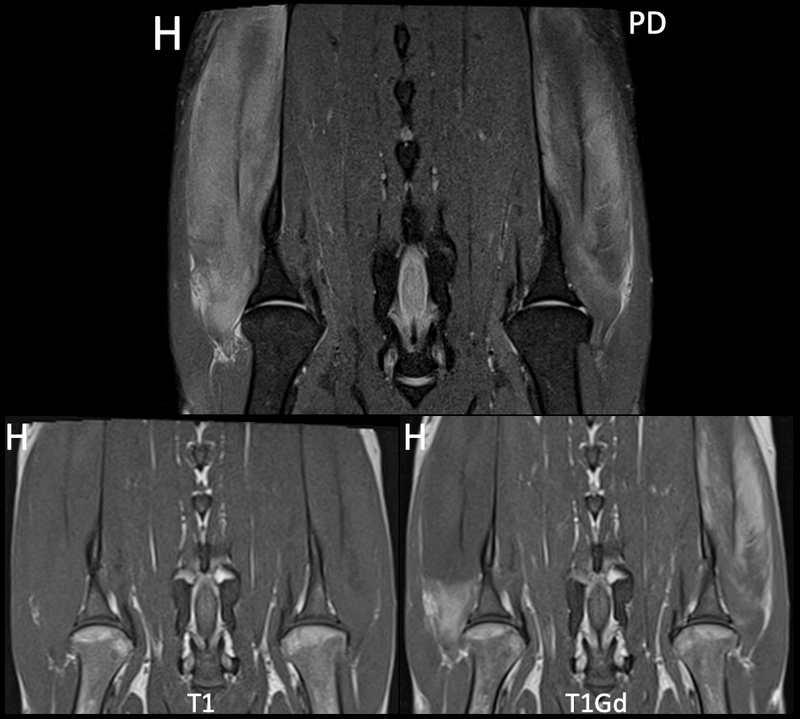

Endelig er vi i gang med kasus igjen, og vi starter høstsesongen med denne godbiten som ble sendt inn til oss fra AniCura Jeløy Dyresykehus. Ha gjerne denne i bakhodet hvis det kommer inn jakthunder eller andre veldig aktive hunder med halthet fra skulder i høst! Signalement: Engelsk setter, Hannhund, 3 år Anamnese: Akutt halt høyre frambein etter jakt Kliniske funn: 4-5/5 grader halt høyre frambein, smerte ved fleksjon av skulder. Ikke medial instabilitet. Mediolaterale og craniocaudale røntgenbilder av begge skuldre er uten unormale funn.